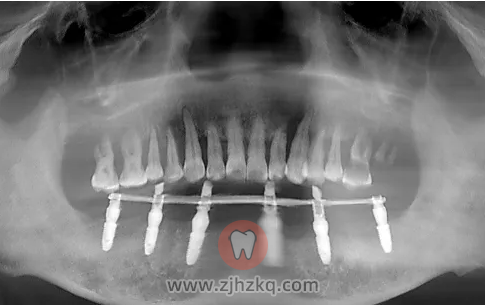

卓先生的口腔情况:全口严重牙周病

上周日,叶院长为卓先生完成了all-on-6手术,半小时修复了半口缺牙。